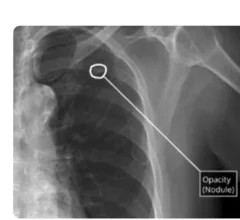

Artificial intelligence (AI) is becoming a crucial component of healthcare to help augment physicians and make them more efficient. In medical imaging, it is helping radiologists more efficiently manage PACS worklists, enable structured reporting, auto detect injuries and diseases, and to pull in relevant prior exams and patient data. In cardiology, AI is helping automate tasks and measurements on imaging and in reporting systems, guides novice echo users to improve imaging and accuracy, and can risk stratify patients. AI includes deep learning algorithms, machine learning, computer-aided detection (CAD) systems, and convolutional neural networks.